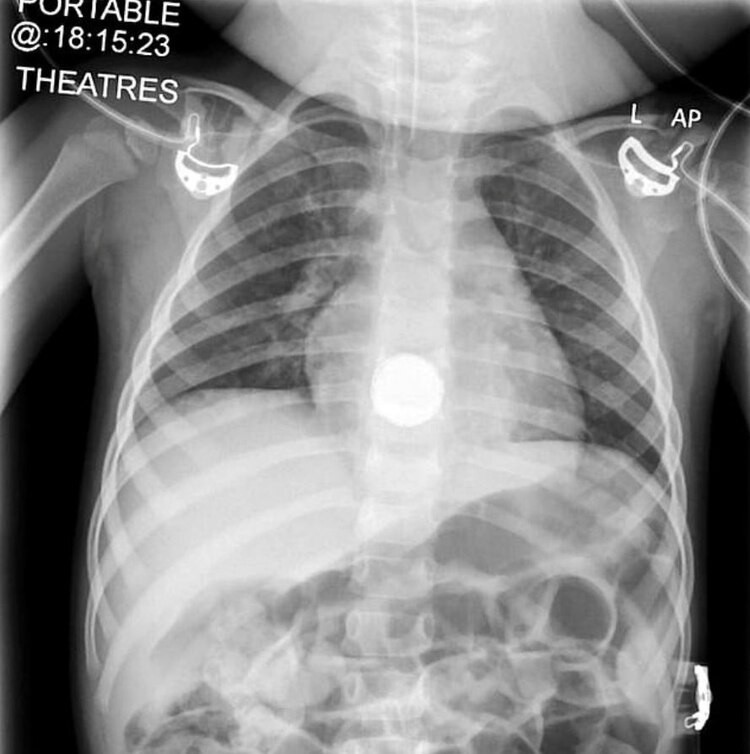

Los médicos vieron en una radiografía la batería de litio que la niña ingirió tan sólo 24 horas antes de la revisión médica, pero que ya le provocaba serios daños en su organismo. Afortunadamente la vieron antes de que la pila le provocara la muerte.